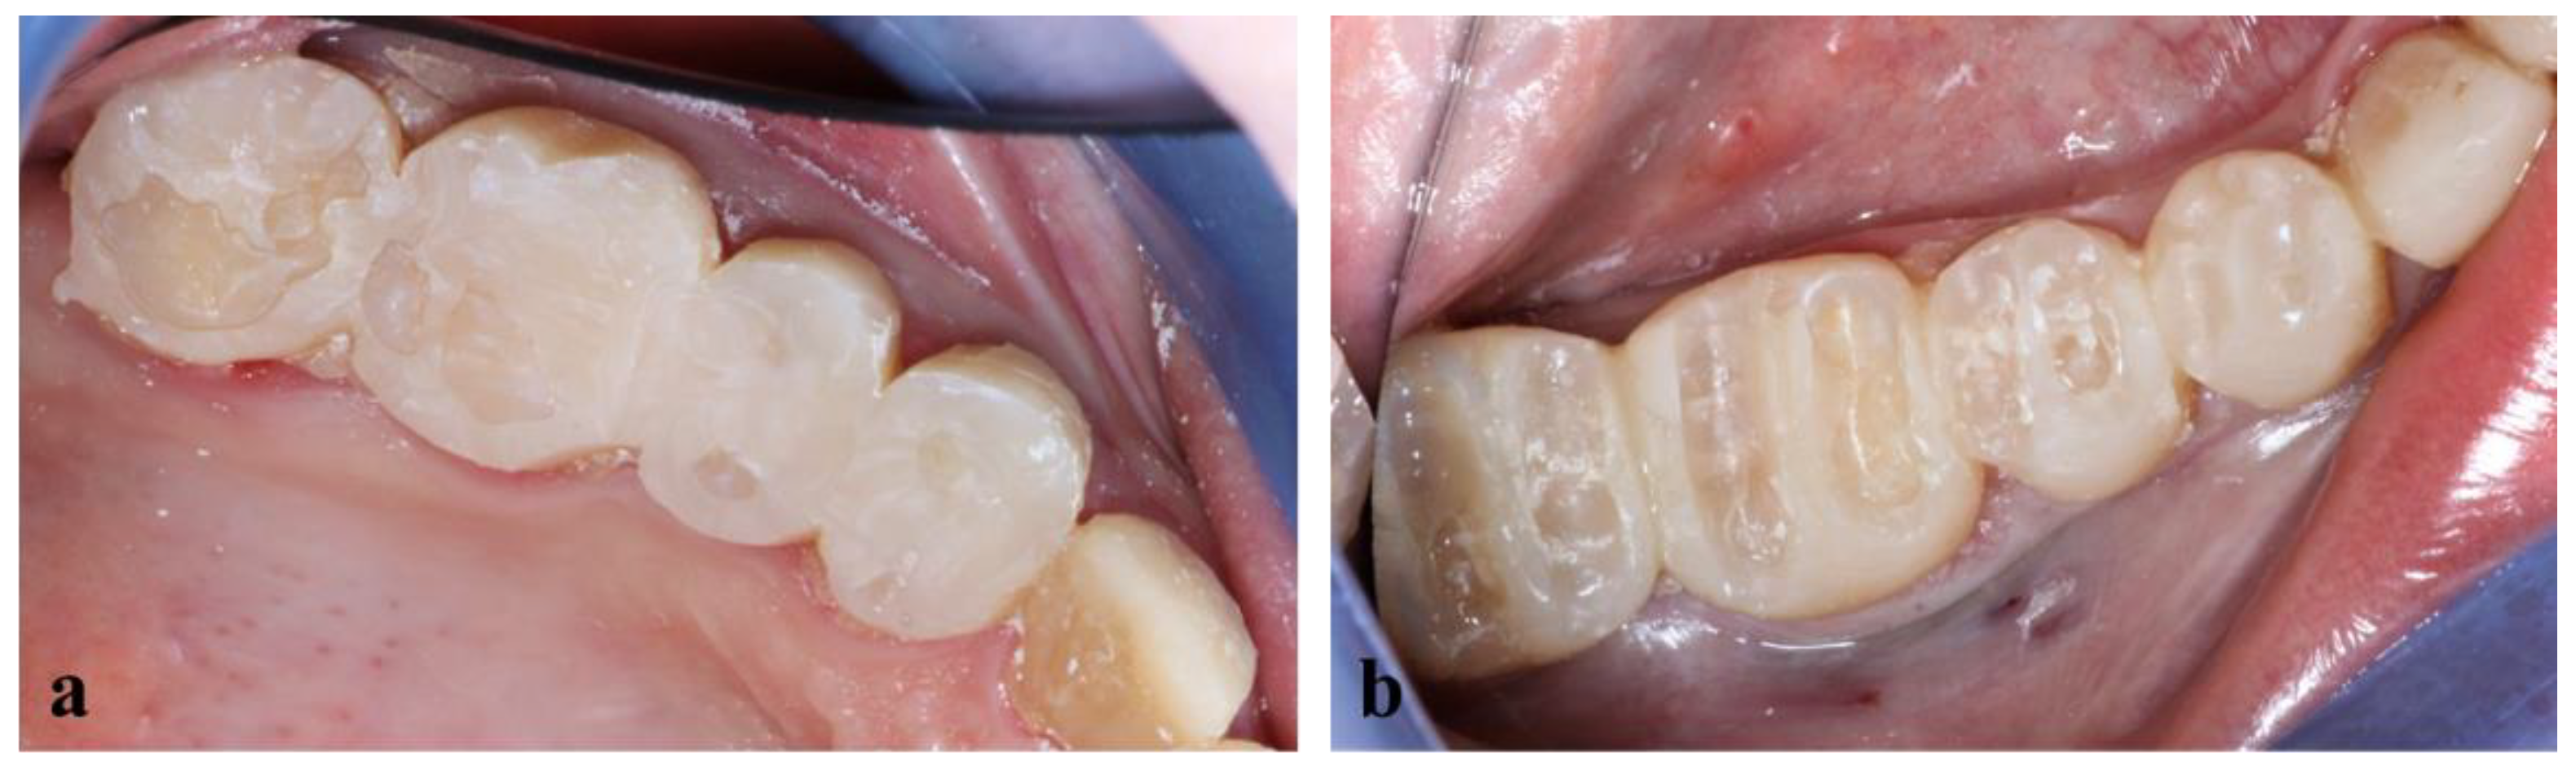

The final view of the upper and lower right side is shown in Figure 14.

Figure 14.

Final view of the right side.